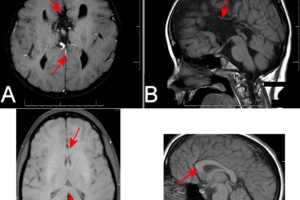

Schizencephaly

Schizencephaly is a developmental abnormality in brain structure consisting of a cleft from the pia into brain parenchyma, lined by heterotopic gray matter. Read more »